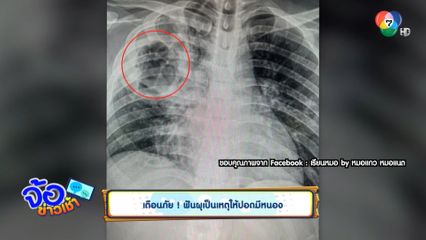

เตือนภัย ! ฟันผุเป็นเหตุให้ปอดมีหนอง

จ้อข่าวเช้า - เตือนภัย ! ฟันผุเป็นเหตุให้ปอดมีหนอง

เตือนภัย ฟันผุเป็นเหตุให้ปอดมีหนอง

ฟันผุ

ปอดมีหนอง

ปอดอักเสบ